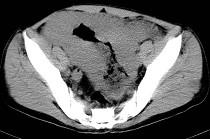

问题 男,23岁,下腹部肿块伴持续性钝痛1月余,影像所见如图,最可能的诊断是()

选项 A.小肠淋巴瘤 B.小肠间质瘤 C.小肠癌 D.小肠转移瘤 E.小肠结核

答案 A